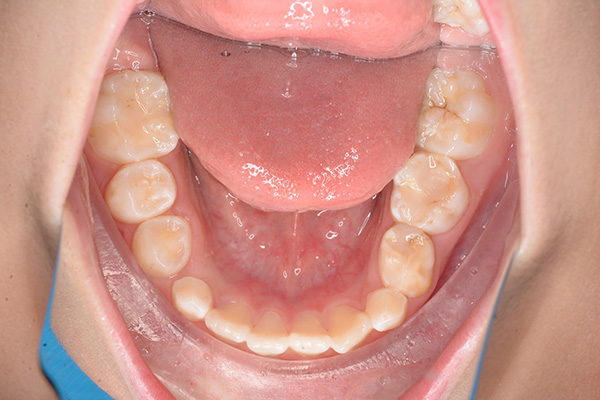

| 主訴 | 上顎前歯のでこぼこ | 診断名 | アングルⅡ級叢生症例 | ||||

|---|---|---|---|---|---|---|---|

| 初診時年齢 | 6歳9ヵ月 | 性別 | 男 | 動的治療期間 | 6ヵ月 | ||

| 既往歴として上顎正中過剰歯(2本)は抜去済み。その影響で上顎右側中切歯は捻転して萌出しており、下顎右側中切歯と早期接触が認められたため2x4(上顎のみブラケット装着)にて前歯部の改善を行った。現在は永久歯列完成まで経過観察を行い、希望があれば口元の突出感を改善するために本格矯正治療を行うことにしている。 | |

| セファロ所見 | 上下顎骨は調和のとれた位置関係を示していたが、頭蓋に対して両顎共に前方に位置していた。上下顎前歯は唇側傾斜していた。 |

| パノラマ所見 | 過剰歯抜歯後は特に問題ない。 |